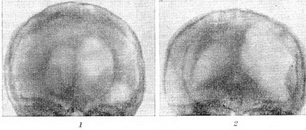

Диференціальна діагностика між супра - і субтенториально розташованими пухлинами не представляє труднощів. На відміну від супратенториально розташованих пухлин, субтенториальные процеси на передньо-задній енцефалограмі не викликають зміщення розширених шлуночків мозку від середньої лінії (рис. 2). В топічної діагностики об'ємних процесів задньої черепної ями істотне значення набуває деформація IV шлуночка і сильвиева водопроводу.

![]() Рис. 2. Зміни форми шлуночків мозку при об'ємному процесі субтенториальной локалізації. |